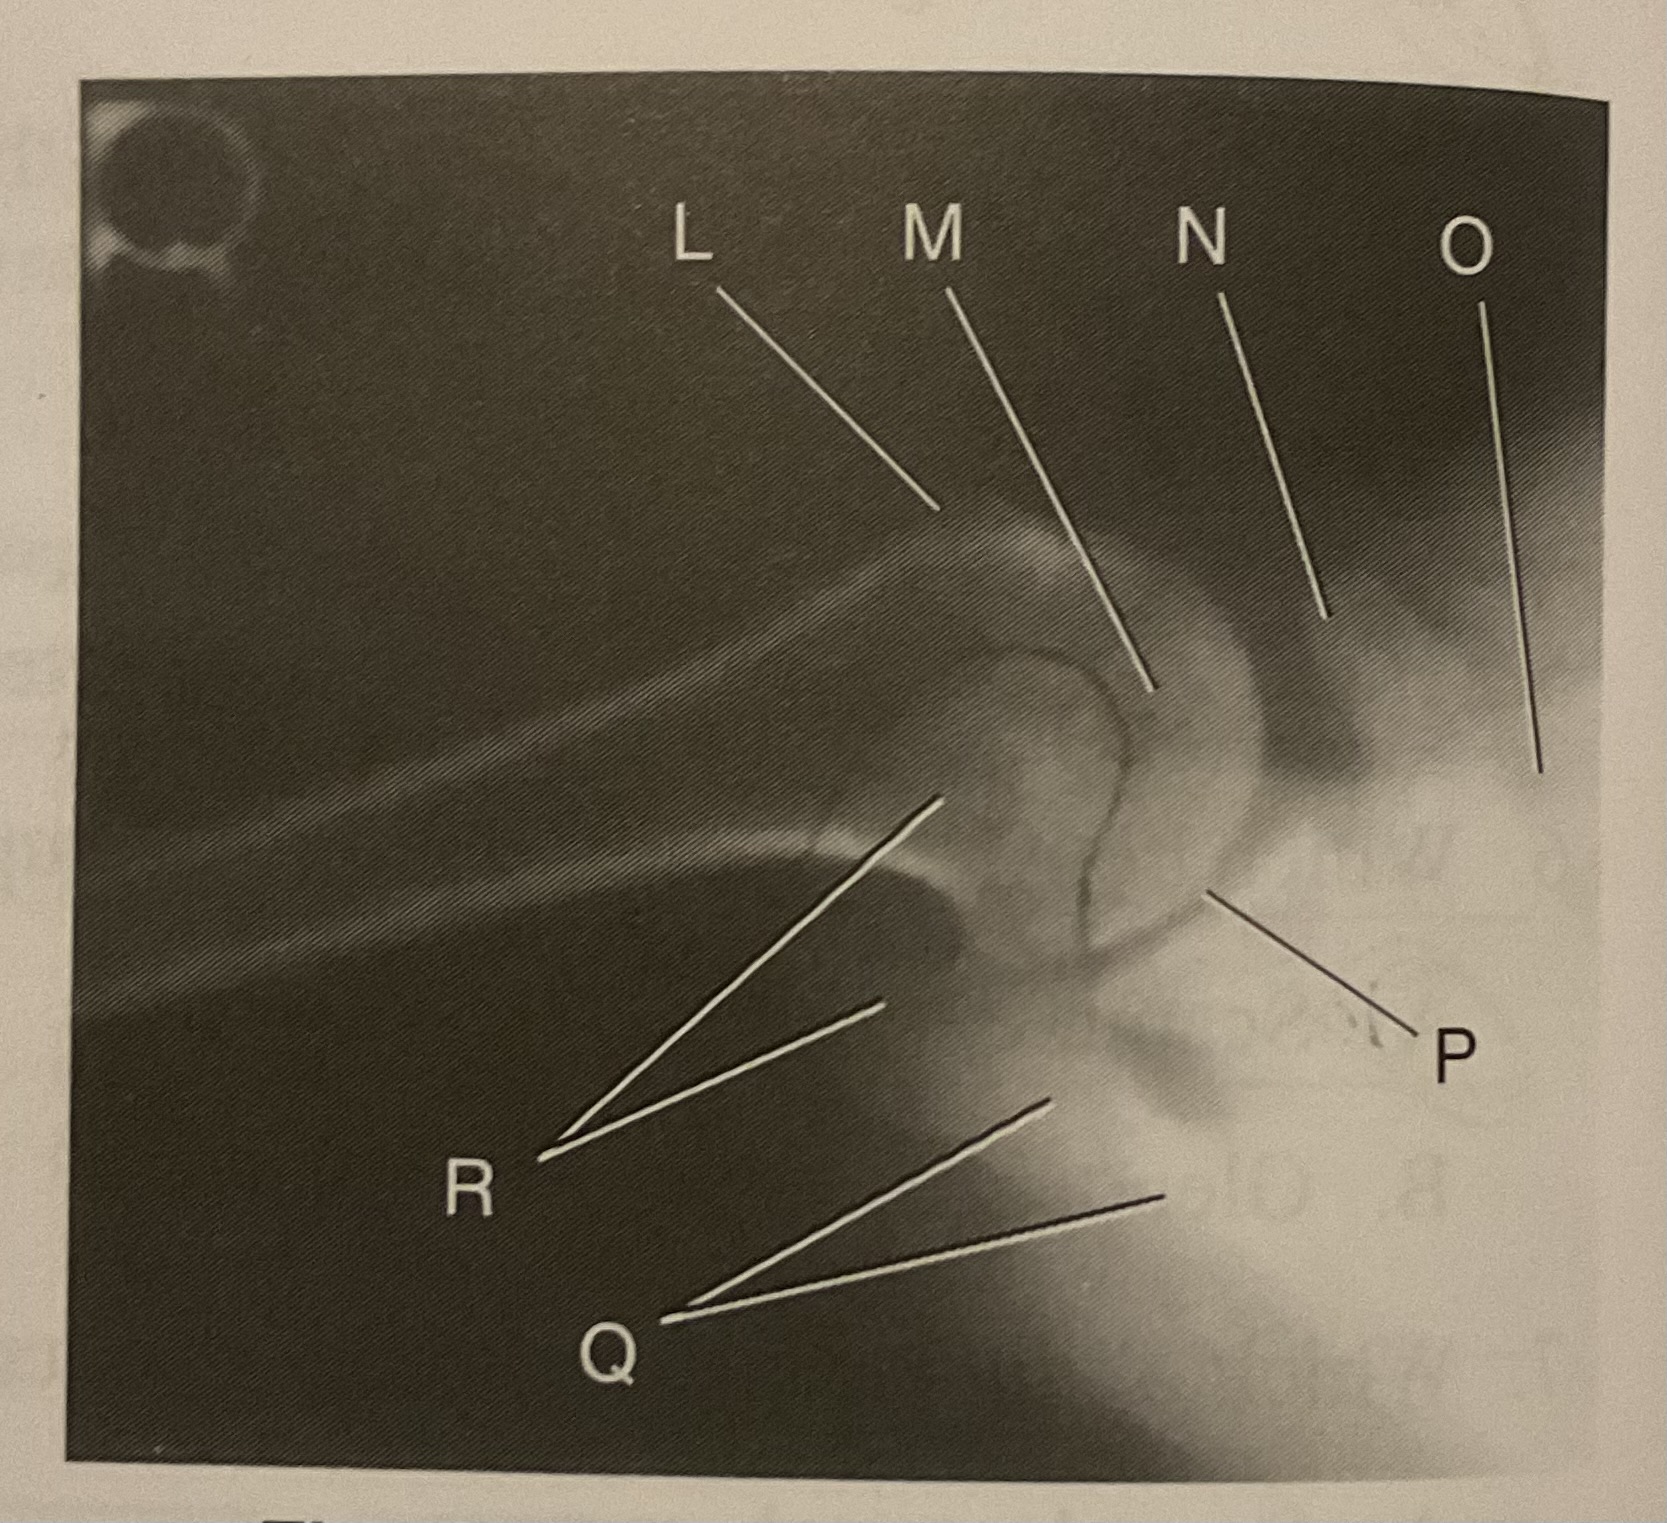

What AP projection does this image represent?

External

L?

Lesser tubercle

M?

Head of humerus

N?

Coracoid process

O?

Clavicle or lateral extremity of clavicle

P?

Glenoid cavity or Scapulohumeral joint

Q?

Spine of scapula

R?

Acromion of scapula

What is the correct term and method for the projection seen in this image?

Inferosuperior axial projection